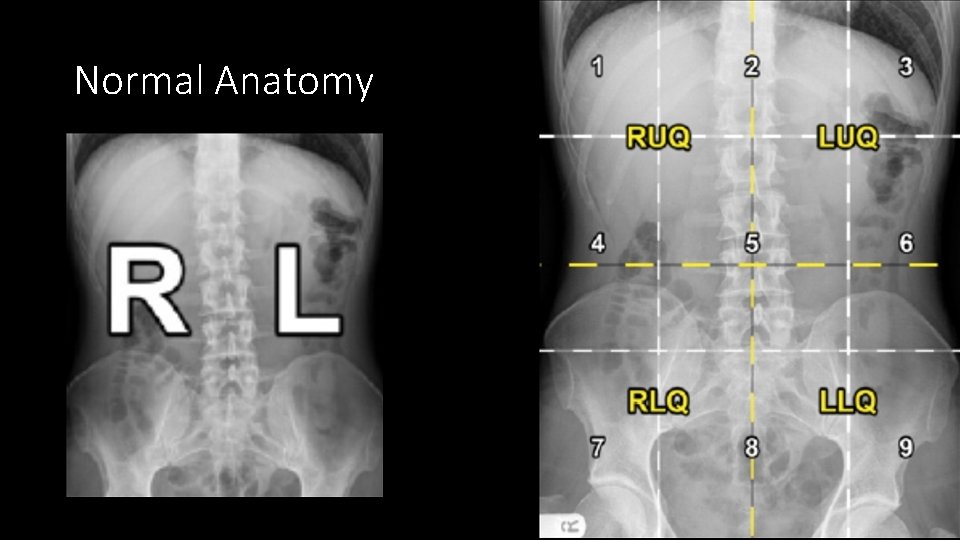

Normal Anatomy

Abdominal viscera • Solid • • Liver Spleen Kidneys and adrenals Pancreas • Hollow • Stomach • Small bowel • Large bowel • Musculoskeletal parts